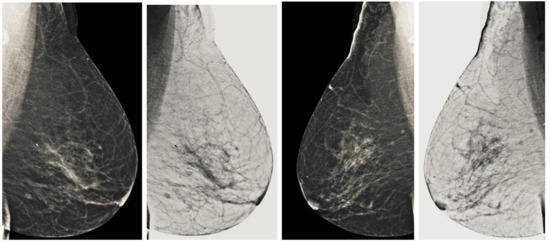

We also measured the PSNR, the image contrast, and the EME of each category of databases, as we analyzed the image in terms of visual observation. The Table 3 shows the performance of our proposed image enhancement method. It can be seen from the Table 3 that our proposed method improved PSNR, contrast, and EME, and this also shows that our method can work on every category of BI-RADS. Because many techniques do not work on higher grade BI-RADS due to the complexity and the images are not of good quality. We obtained an average improvement in PSNR, contrast, and EME in the Table 4. For more observations, we analyzed the visual image of each category and we analyzed the CC and MLO of each category as shown in the Figure 7, Figure 8, Figure 9, Figure 10, Figure 11, Figure 12, Figure 13, Figure 14, Figure 15 and Figure 16. From the figures, every detail of image of every category can be observed, leading to better segmentation of the abnormal region. This image enhancement technique can be used as preprocessing steps for the detection of breast cancer. It is a very fast processing algorithm and it takes on 21.13 s. It gives opportunity to medical experts to analyze the mammogram images very quickly to propose the timely treatment.

Figure 7.

Analysis of CC view of BI-RADS-1 mammogram images.

Figure 8.

Analysis of MLO view of BI-RADS-1 mammogram images.